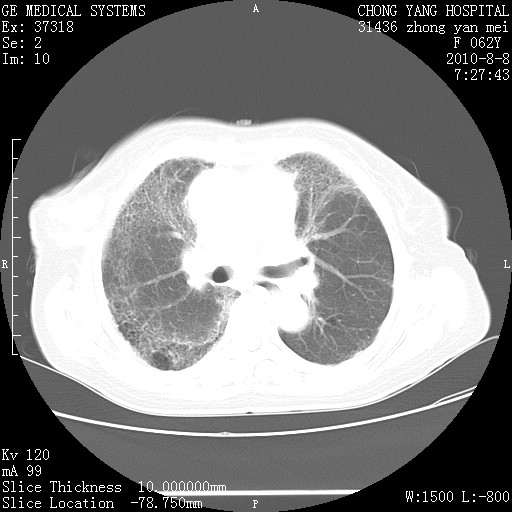

标题: CT28269:F62Y咳嗽胸痛数月。 [打印本页]

标题: CT28269:F62Y咳嗽胸痛数月。

两肺弥漫性间质纤维化伴继发性支扩。

考虑特发性肺间质纤维化

考虑两肺间质性肺炎并肺间质纤维化。

肺间质纤维化合并感染

双肺间质纤维化合并感染、肺气肿

双肺间质纤维化

特发性的肺间质纤维化

另见右乳腺似有小钙化灶,建议进一步检查。

特发性肺间质纤维化合并感染!

两肺间质纤维化并牵拉性细支气管扩张。

考虑两肺间质性肺炎并肺间质纤维化,肺气囊形成。